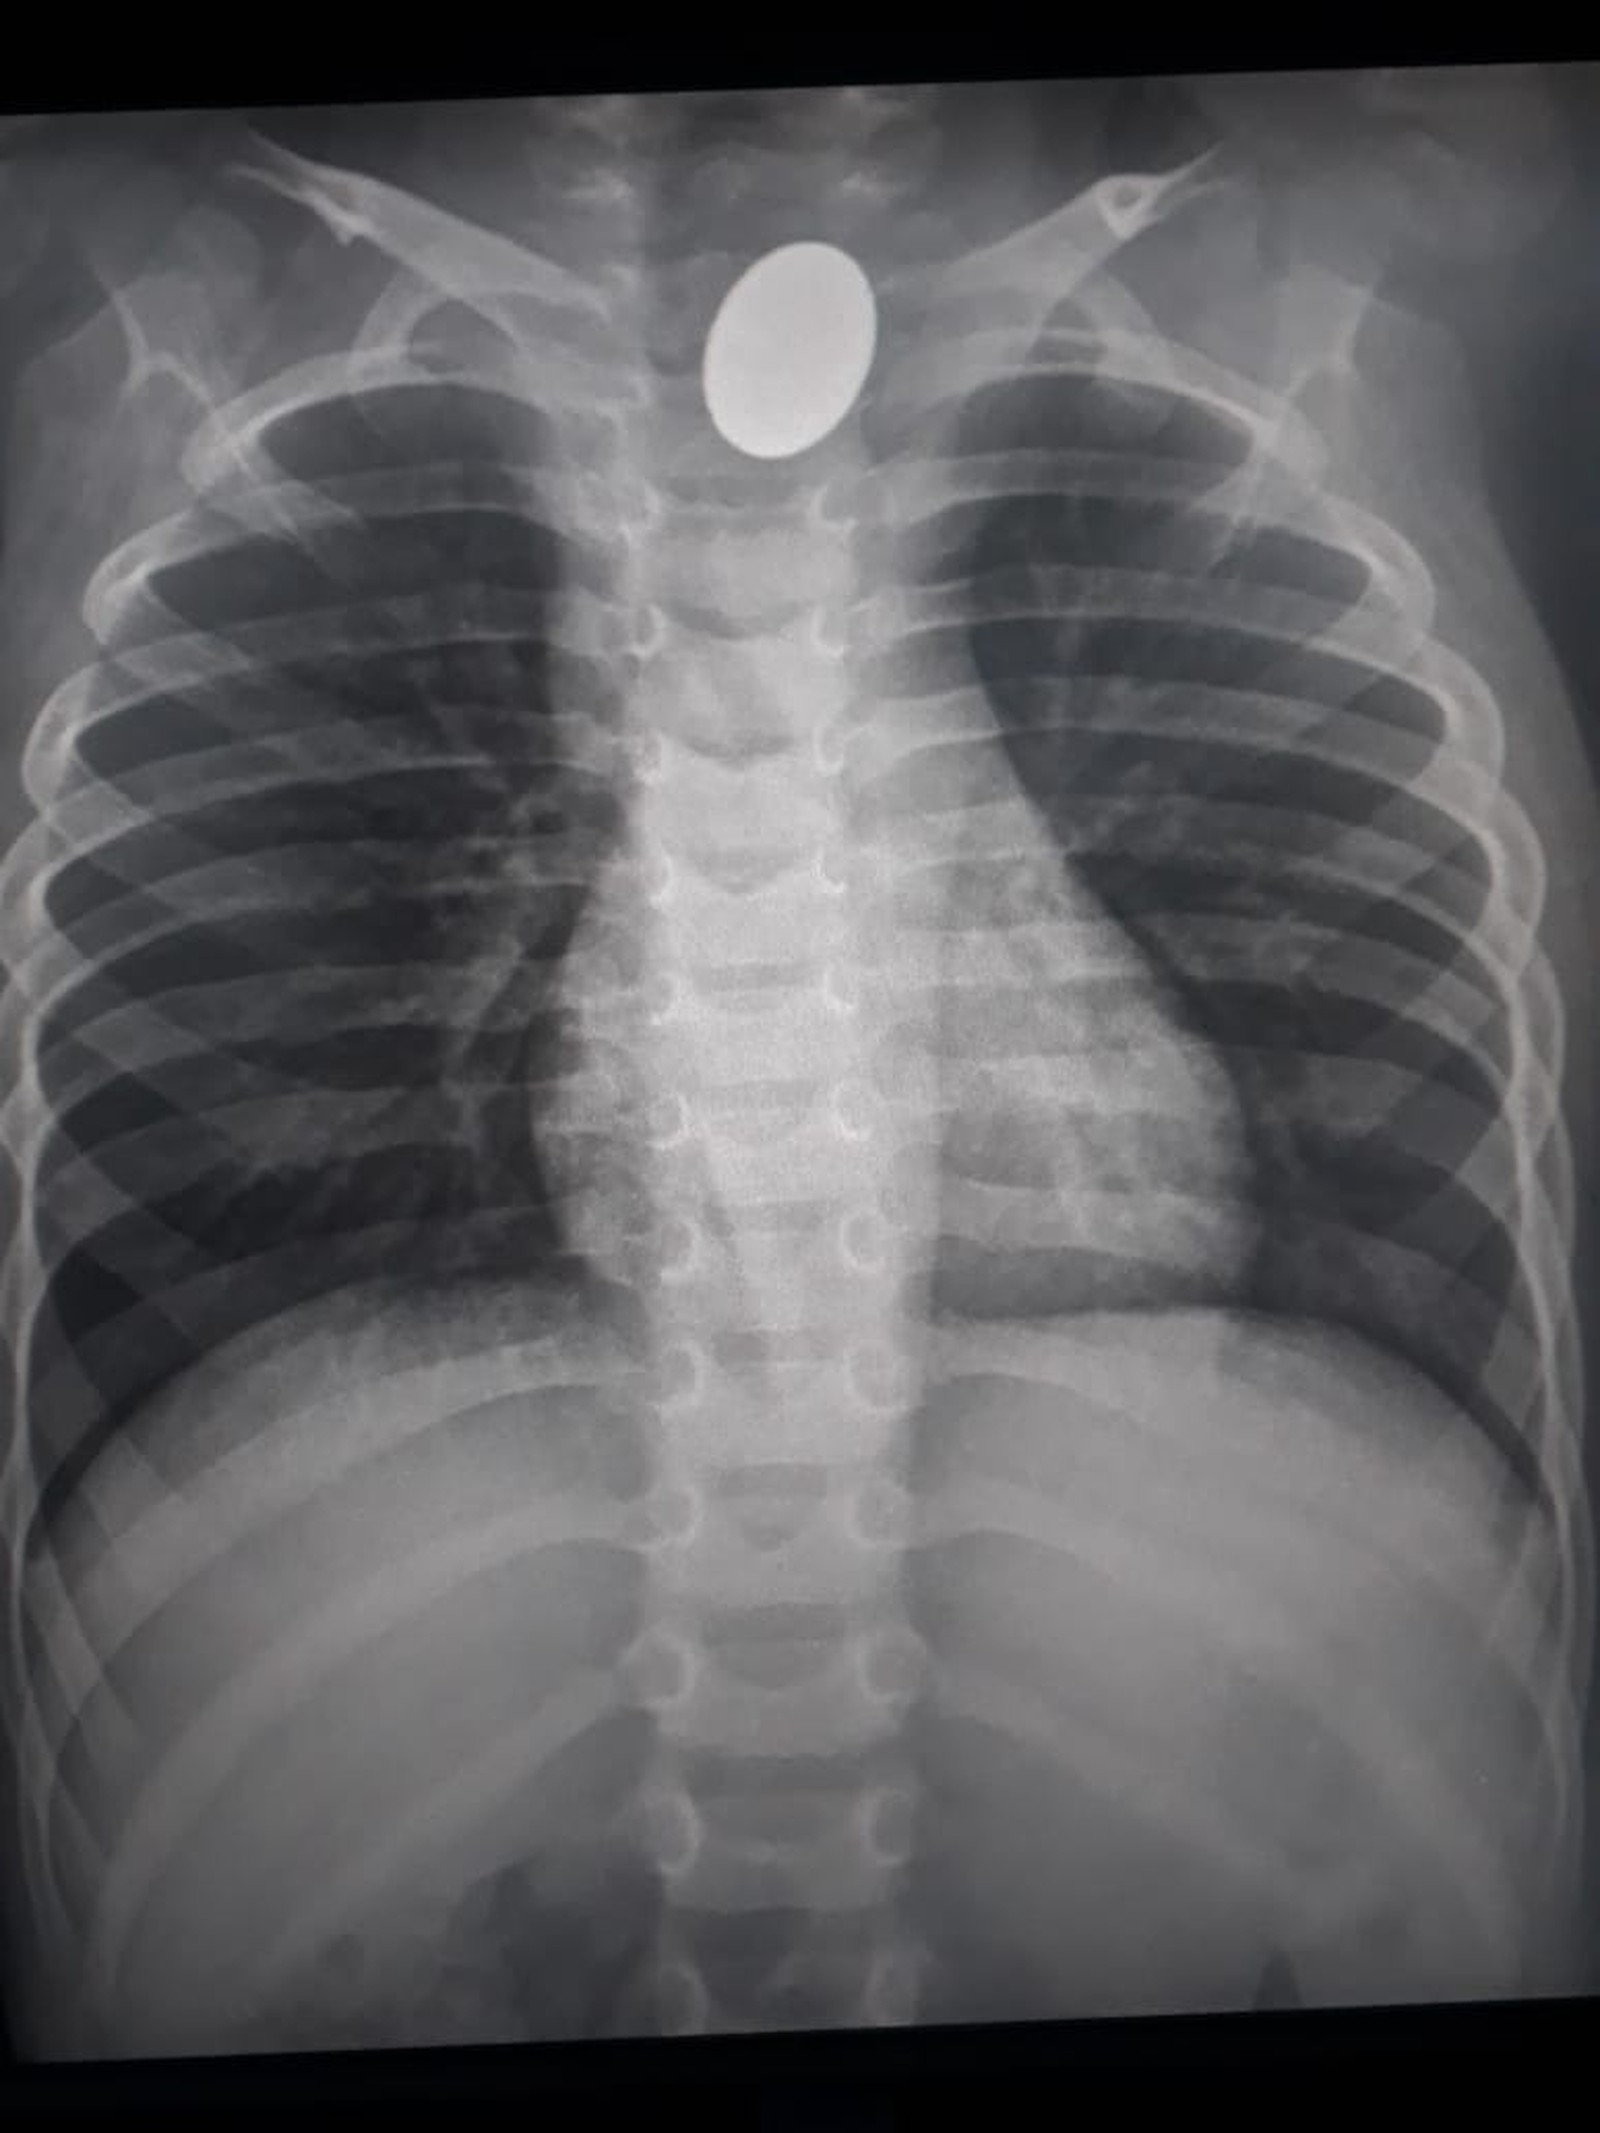

O drama da família do pequeno Levi Daniel, de apenas 3 anos, começa no domingo (16). A criança começou a apresentar uma espécie de “ronco”, que causava dificuldades para respirar. Os pais o levaram até a Unidade de Pronto Atendimento (UPA) de Parnamirim. Segundo os pais de Levi, após exame de radiografia, os médicos identificaram um objeto na garganta do garoto. Na segunda (17), ele foi transferido ao Hospital Walfredo Gurgel, em Natal, para ser submetido a uma endoscopia.

“Até agora nenhuma resposta clara foi dada para a gente. Nós não sabemos o que é esse ‘objeto estranho’. A gente achava que depois do laudo do Itep ia saber, mas nem o laudo diz. Perder um filho é muito angustiante e é pior ainda quando não se tem certeza do que realmente aconteceu. A gente suspeita que possa ter sido uma moeda ou peça de brinquedo, mas até agora não sabemos nada”, disse Lairton Silva, pai de Levi Daniel.